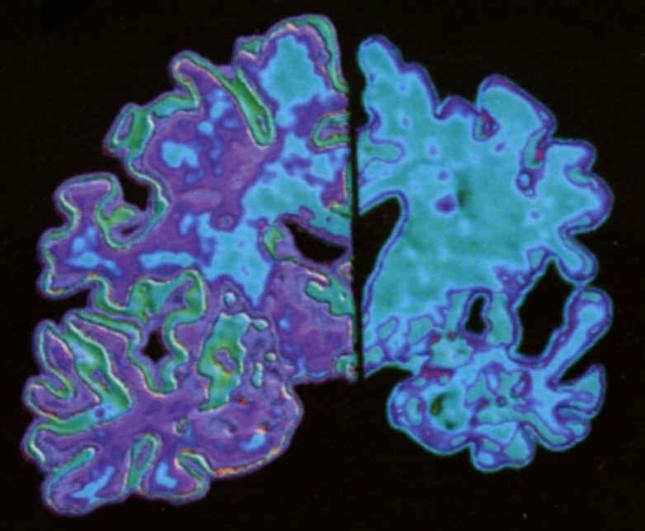

Grande scoperta, svelato come nasce l’Alzheimer. Nuovi percorsi terapeutici

Una grande scoperta, svelato finalmente come nasce l’Alzheimer, una delle malattie più temute dalla popolazione mondiale. L’Alzheimer non ha più misteri per la scienza. La ricerca dell’Istituto Europeo per la Ricerca sul Cervello ha permesso di ricostruire, il meccanismo che porta allo sviluppo dell’Alzheimer.

Il punto di partenza è stato lo studio di una cellula di criceto: il sito in cui si realizzano le molecole tossiche che scatenano l’Alzheimer. Composte da pochi frammenti di Dna, detti oligomeri, queste molecole formano la proteina beta-amiloide, responsabile delle placche tipiche della malattia. Tutto questo può portare ad individuare nei malati nuovi percorsi terapeutici per cercare di combattere la mallattia.